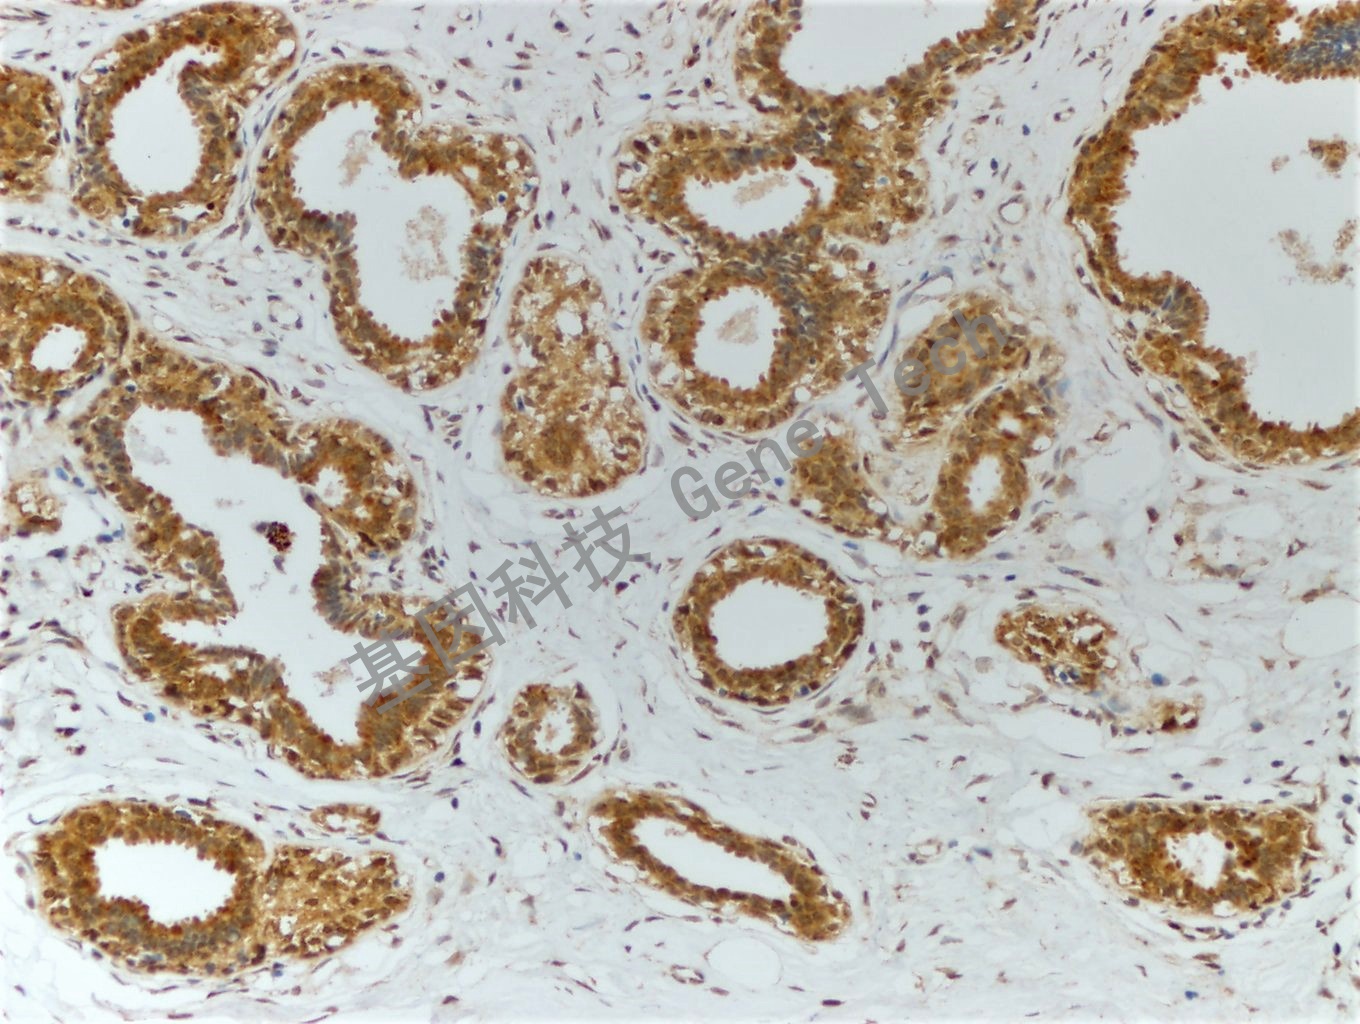

| 乳腺癌石蠟切片,用 PTEN(GT2010)染色,細胞漿/細胞核陽性,DAB 顯色。 | ||

| 預處理:高pH熱修復 | 陽性部位:細胞漿/細胞核 | 陽性對照:乳腺癌 |